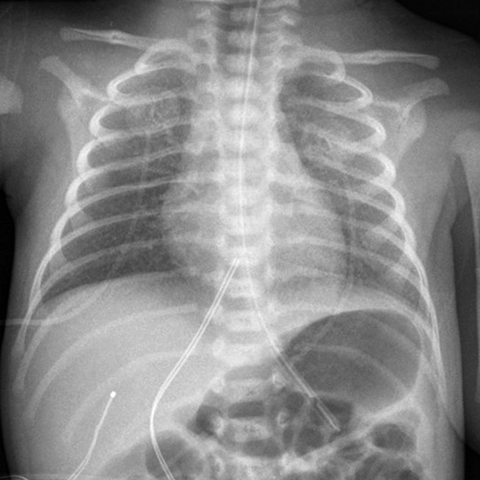

Portable AP Chest Radiograph [2 of 3]

Lines

Lines and Labels